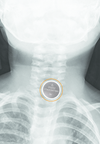

When a child swallows a coin lithium button battery, often the battery will get stuck in the child’s throat. The child’s saliva will trigger an electrical current, which causes a chemical reaction that can severely burn their esophagus in as little as two hours. And once burning begins, damage can continue even after the battery is removed.

The number of coin-sized button battery swallowing cases resulting in serious injury or death, more than quadrupled from 2006 - 2010 compared to the five years prior. Children age 4 and under are at the greatest risk.